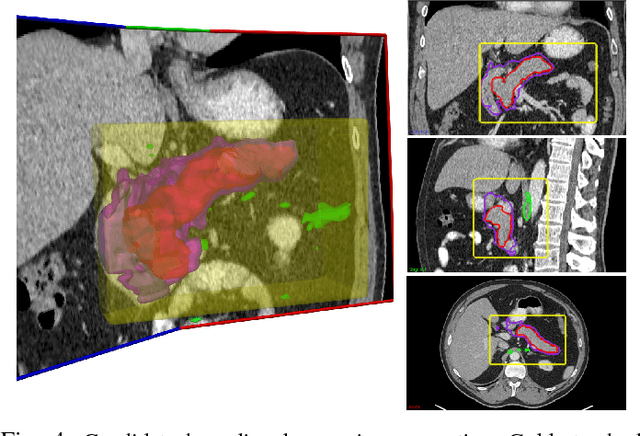

Abstract:Accurate and automatic organ segmentation from 3D radiological scans is an important yet challenging problem for medical image analysis. Specifically, the pancreas demonstrates very high inter-patient anatomical variability in both its shape and volume. In this paper, we present an automated system using 3D computed tomography (CT) volumes via a two-stage cascaded approach: pancreas localization and segmentation. For the first step, we localize the pancreas from the entire 3D CT scan, providing a reliable bounding box for the more refined segmentation step. We introduce a fully deep-learning approach, based on an efficient application of holistically-nested convolutional networks (HNNs) on the three orthogonal axial, sagittal, and coronal views. The resulting HNN per-pixel probability maps are then fused using pooling to reliably produce a 3D bounding box of the pancreas that maximizes the recall. We show that our introduced localizer compares favorably to both a conventional non-deep-learning method and a recent hybrid approach based on spatial aggregation of superpixels using random forest classification. The second, segmentation, phase operates within the computed bounding box and integrates semantic mid-level cues of deeply-learned organ interior and boundary maps, obtained by two additional and separate realizations of HNNs. By integrating these two mid-level cues, our method is capable of generating boundary-preserving pixel-wise class label maps that result in the final pancreas segmentation. Quantitative evaluation is performed on a publicly available dataset of 82 patient CT scans using 4-fold cross-validation (CV). We achieve a Dice similarity coefficient (DSC) of 81.27+/-6.27% in validation, which significantly outperforms previous state-of-the art methods that report DSCs of 71.80+/-10.70% and 78.01+/-8.20%, respectively, using the same dataset.